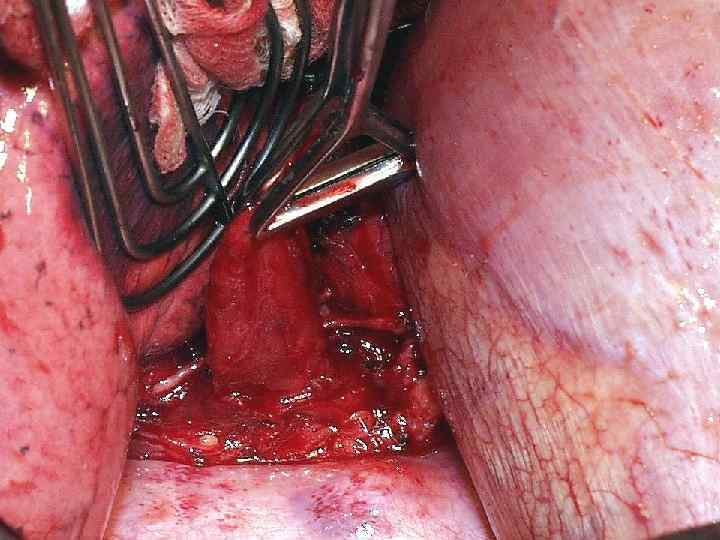

Дивертикулэктомия

Больная П. 49 л. 21. 03. 2005 – дивертикулэктомия.